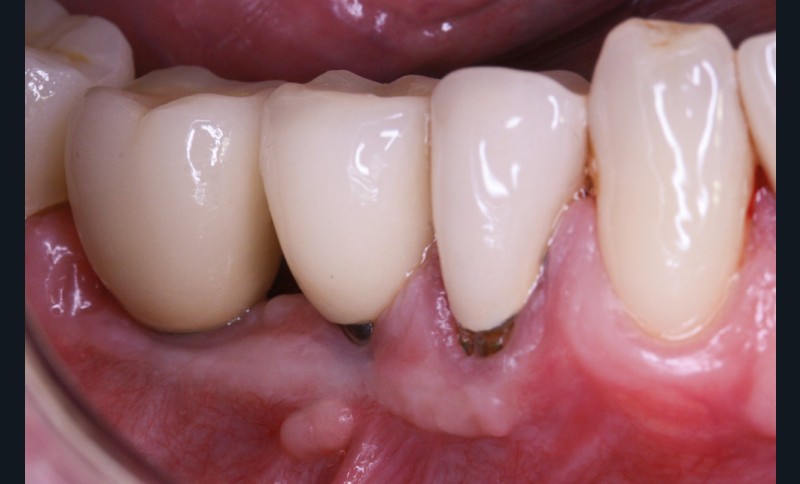

La greffe épithélio-conjonctive (GEC) [7, 8] consiste au remplacement du tissu parodontal existant par un greffon épithélio-conjonctif dont l’indication principale est l’augmentation en hauteur et en épaisseur du tissu kératinisé (fig. 2). Elle peut aussi être utilisée dans le recouvrement radiculaire (avec des résultats en termes de recouvrement inférieurs à ceux des techniques de greffe de conjonctif enfouie), l’aménagement des crêtes édentées, l’aménagement péri-implantaires [9, 10] (fig. 3), ou en association avec un traitement ortho-parodontal [11]. Le principal défaut de cette technique est son aspect inesthétique ; elle sera donc réservée à des zones non visibles comme les incisives mandibulaires ou les zones postérieures.